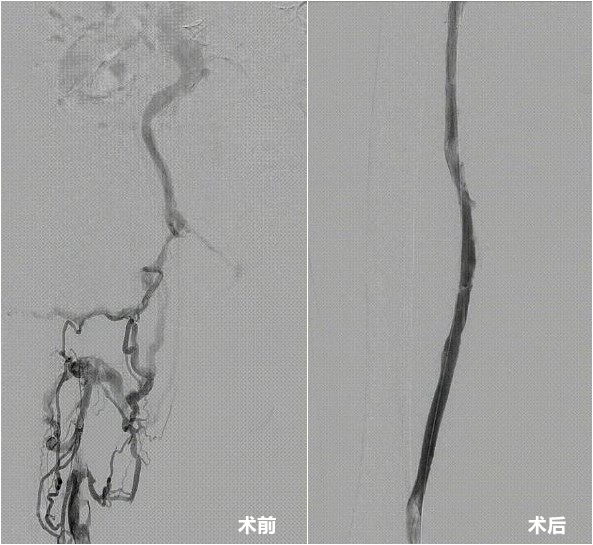

患者术前术后下肢静脉造影对比。

经造影显示,赵爷爷的右下肢已有多条静脉节段性血栓形成,而且血栓不仅在腿部蔓延,还一直向上长进了髂静脉(位于盆腔内深部的大血管)。“血栓把人体的大静脉完全堵塞了,就好比主干道严重堵车,只有小路能通行,血管梗阻的严重程度可想而知,老人急需手术将血栓取出。”厦心血管外科主任庄晖表示,如不及时处理,将严重影响患者今后生活质量,可能会引起反复的下肢麻木、肿胀,甚至溃烂、坏疽等下肢血栓栓塞后遗症,急性肺栓塞等致死性并发症的可能性也大大增加。

经全面评估,厦心血管外科团队决定采用参与研发的国内首款专门为下肢静脉血栓治疗设计的取栓系统开展手术。术中,细小的导管精准抵达栓塞部位,凭借独特的结构设计高效抽吸,如同“血管清道夫”一般,快速清除了大量新鲜与顽固的陈旧血栓。反复操作确认血管畅通无阻后,赵爷爷堵塞已久的“生命通道”终于重建。同日,庄晖团队运用同一器械,再次成功救治另一名70岁高龄的复杂血栓患者。相比传统治疗方式,新器械手术时间短、取栓效率高,降低了血管内膜损伤和出血并发症的风险,为患者(尤其是高龄、危重患者)提供了更优解。